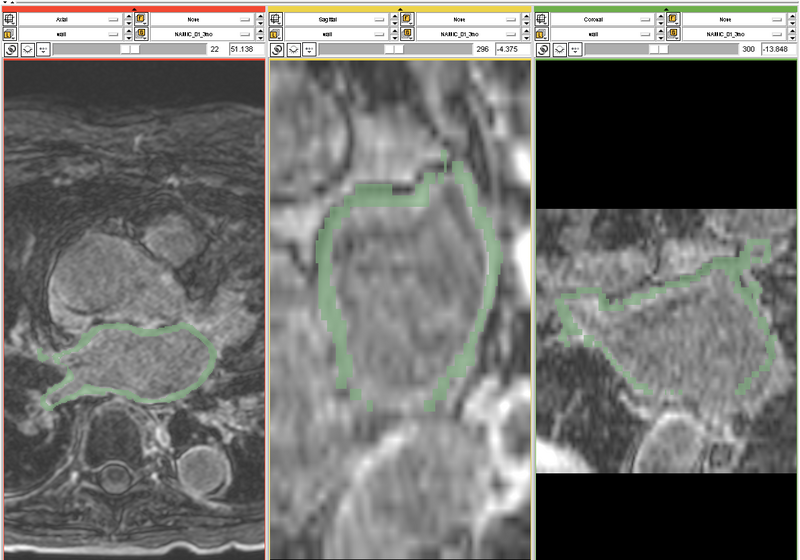

One of the results is shown below: